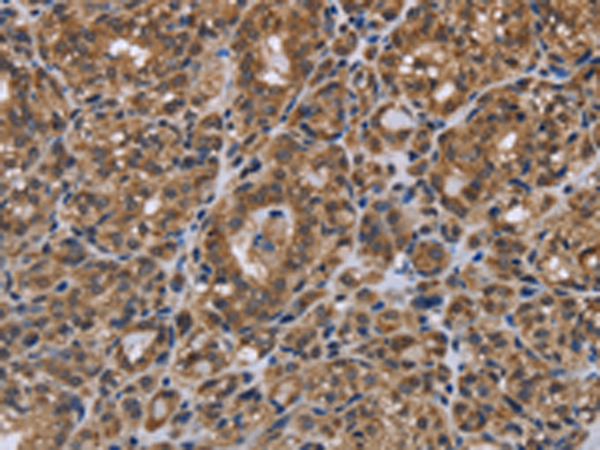

分类: 科研抗体货号: P01330别名: EL; EDL; PRO719应用: IHC反应种属: Human